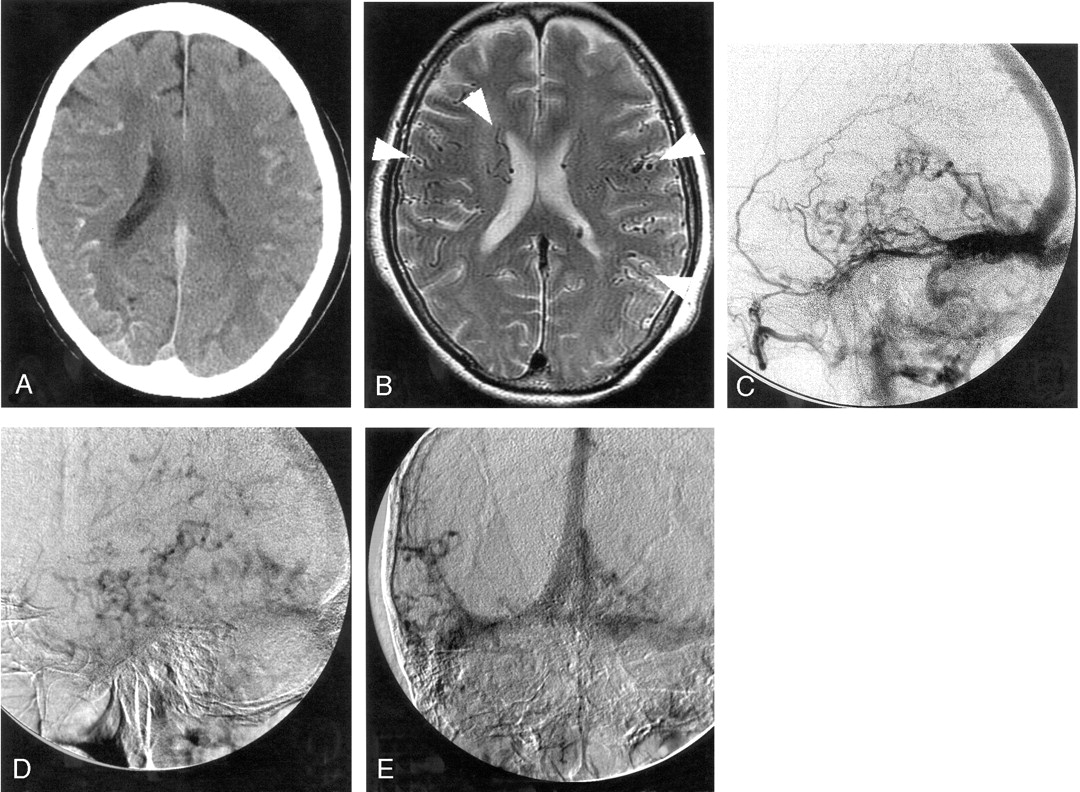

Case 2.

A, CT scan shows curvilinear calcification in the cortico-medullary junction at the bottom of cerebral sulci bilaterally but more predominantly in right cerebral hemisphere.

B, T2-weighted MR image shows prominent cortical and subependymal veins (arrowheads), which possibly suggests an arteriovenous shunt with cortical venous reflux as well as hyperintensity in deep white matter that was more apparent on the right.

C–E, Serial right external carotid angiograms (C and D, lateral view; E, frontal view) show enlargement of the middle meningeal artery with early filling of the transverse sinus and retrograde filling of the straight and superior sagittal sinuses. Cortical venous reflux is also evident in the later phase.